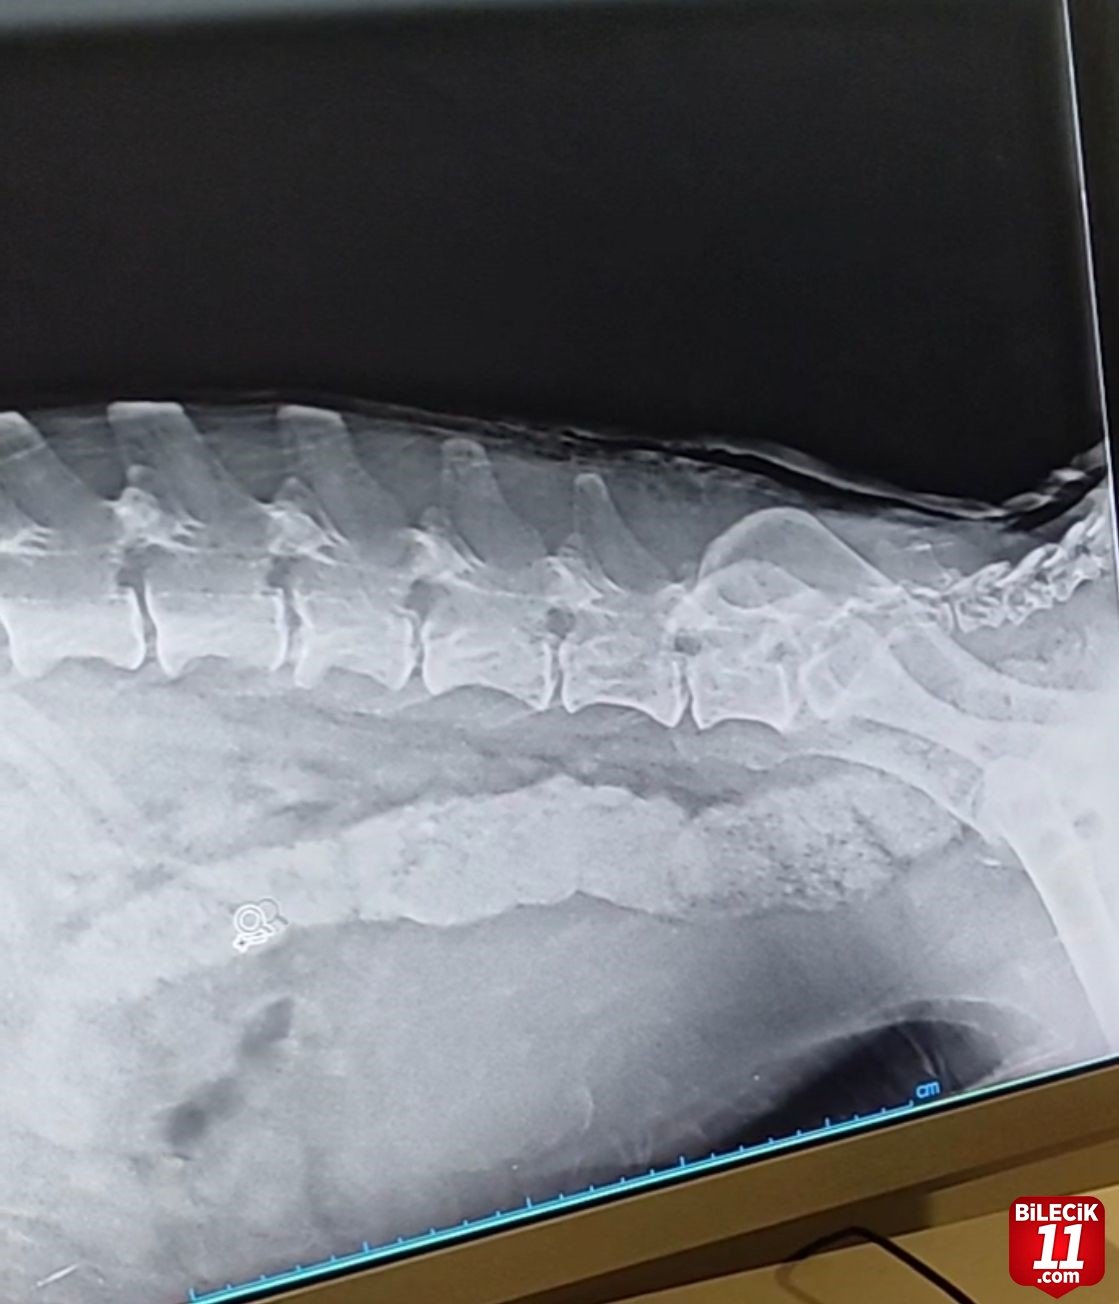

Eskişehir’de arka ayakları kısmi felç olan köpek, hayvanseverlerin kendi imkânlarıyla tedavi ettirmesiyle 15 günde sağlığına kavuştu.

Odunpazarı ilçesinin Sarısungur Mahallesi’nde bulunan şehir çöplüğüne besleme maksadıyla giden hayvanseverler, bir köpeğin ayağa kalkamadığını fark etti. Hayvanın acı çektiğini anlayan gönüllüler, köpeğin araç çarpması veya benzeri bir durumdan dolayı sakatlık yaşadığın öngördü. Daha sonra battaniyeye sardıkları köpeği kendi araçlarıyla veterinere götüren hayırsever vatandaşlar, çekilen röntgenler sonrası talihsiz hayvanın arka ayaklarının kısmi felç olduğunu öğrendi. Panda ismi verilen köpeğe veterinerlerce zaman kaybetmeden ilaç ve diğer tedavilerine başlanıldı. Hayvanseverlerin kedi imkânlarıyla yaptırılan tedavilerin maliyeti 7 bin lirayı buldu. 15 gün boyunca bakılan Panda, tedavinin ardından eski sağlığına kavuşarak 4 ayağının üzerinde durmaya başladı. – İHA